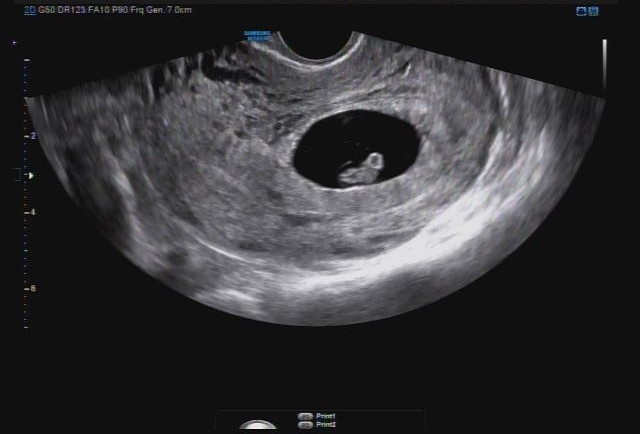

[임신12주-16주] 1차&2차 기형아검사+태동

안녕하세요~18주에 들어선 지금 배는 더 나오기 시작했지만 컨디션은 좋네요♡ 이렇게 작고 형체도 알아볼 ...